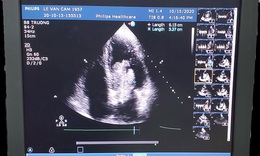

Nguy cơ đột tử do u nhầy trong tim

Bệnh thường gặp - 01/08/2018 10:46SKĐS - Mới đây, các bác sĩ Trung tâm tim mạch Bệnh viện Đại học Y Dược TP.HCM (BV. ĐHYD) đã cắt thành công khối u nhầy lớn với kích thước 6x4x3 cm trong tim người bệnh bằng phương pháp phẫu thuật tim nội soi.